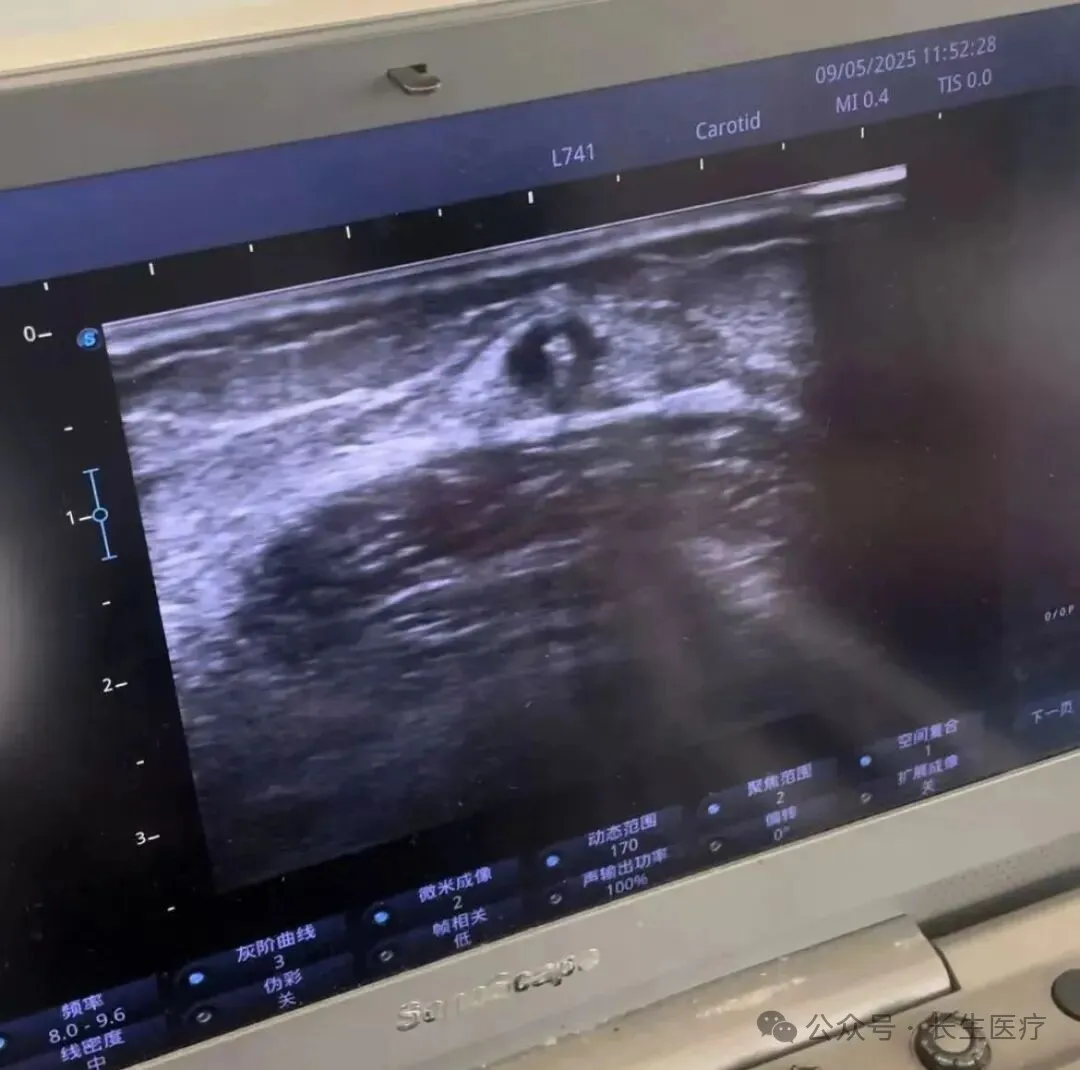

长生医疗小百科:黑龙江长江肾病医院血管通路门诊主任陈波医生分享——超声引导下内瘘穿刺技术的要点

对于适应症合适的病人,我们采取超声引导下,动静脉内瘘穿刺。我科有成熟的血管通路手术团队,结合超声引导下经皮静脉球囊扩张术穿刺技术。通过医生与护士合作,将只有血管鞘组针一半长度的透析穿刺针,在超声引导下,成功置入患者血管。穿刺针短、粗、硬,不同于鞘组穿刺针,透析针穿刺可调节范围小,针体粗,损伤大,务必保证一次成功。

穿刺过程中,超声探头实时显示结合血管横截面与纵切面,观察针尖与皮下组织关系,走形轨迹与血管位置,使针尖在血管12点方向进入,观察回血情况观察针体与血管壁关系,避免损伤血管及周围组织。